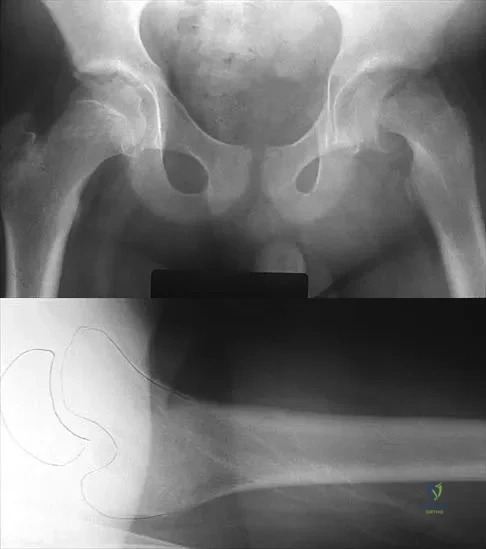

A 52-year-old woman reports mild pain localized to the left sternoclavicular joint. History is notable for chronic renal failure requiring dialysis for the last 5 years. A clinical photograph, chest radiograph, and bone scan are shown in Figures 58a through 58c. What is the most likely diagnosis?

Explanation